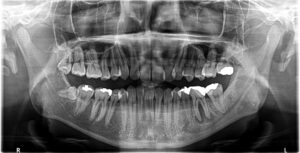

初診時レントゲン

下顎左側第一大臼歯(赤丸)に親指の頭ぐらいの大きさの根尖病変が認められます。